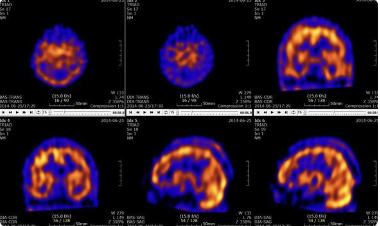

Does this image make sense?

A

yes

Q

what does the circled part of the image show?

it shows a normal perfusion

this happens during rest